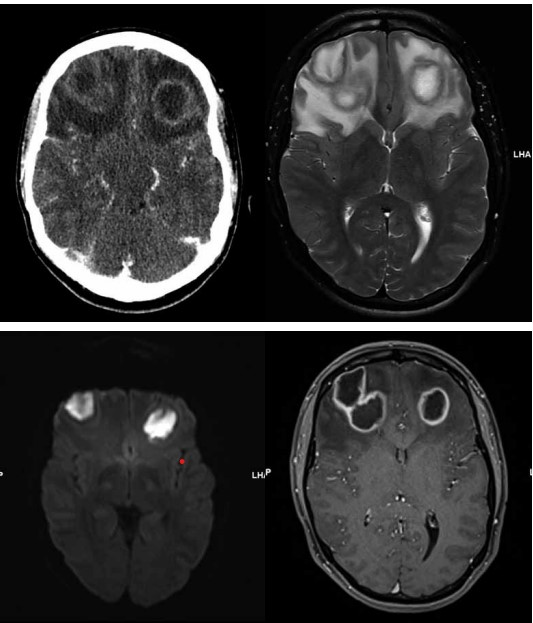

Considere o caso clínico a seguir para responder à questão.

Paciente do sexo masculino, de 23 anos de idade, vem ao pronto-socorro com queixa de cefaleia e leve confusão mental com início há 7 dias.

O paciente realizou tomografia e ressonância magnética do encéfalo apresentadas a seguir:

(Arquivo pessoal; imagem usada com autorização)

Sobre os achados mencionados, assinale a alternativa correta.